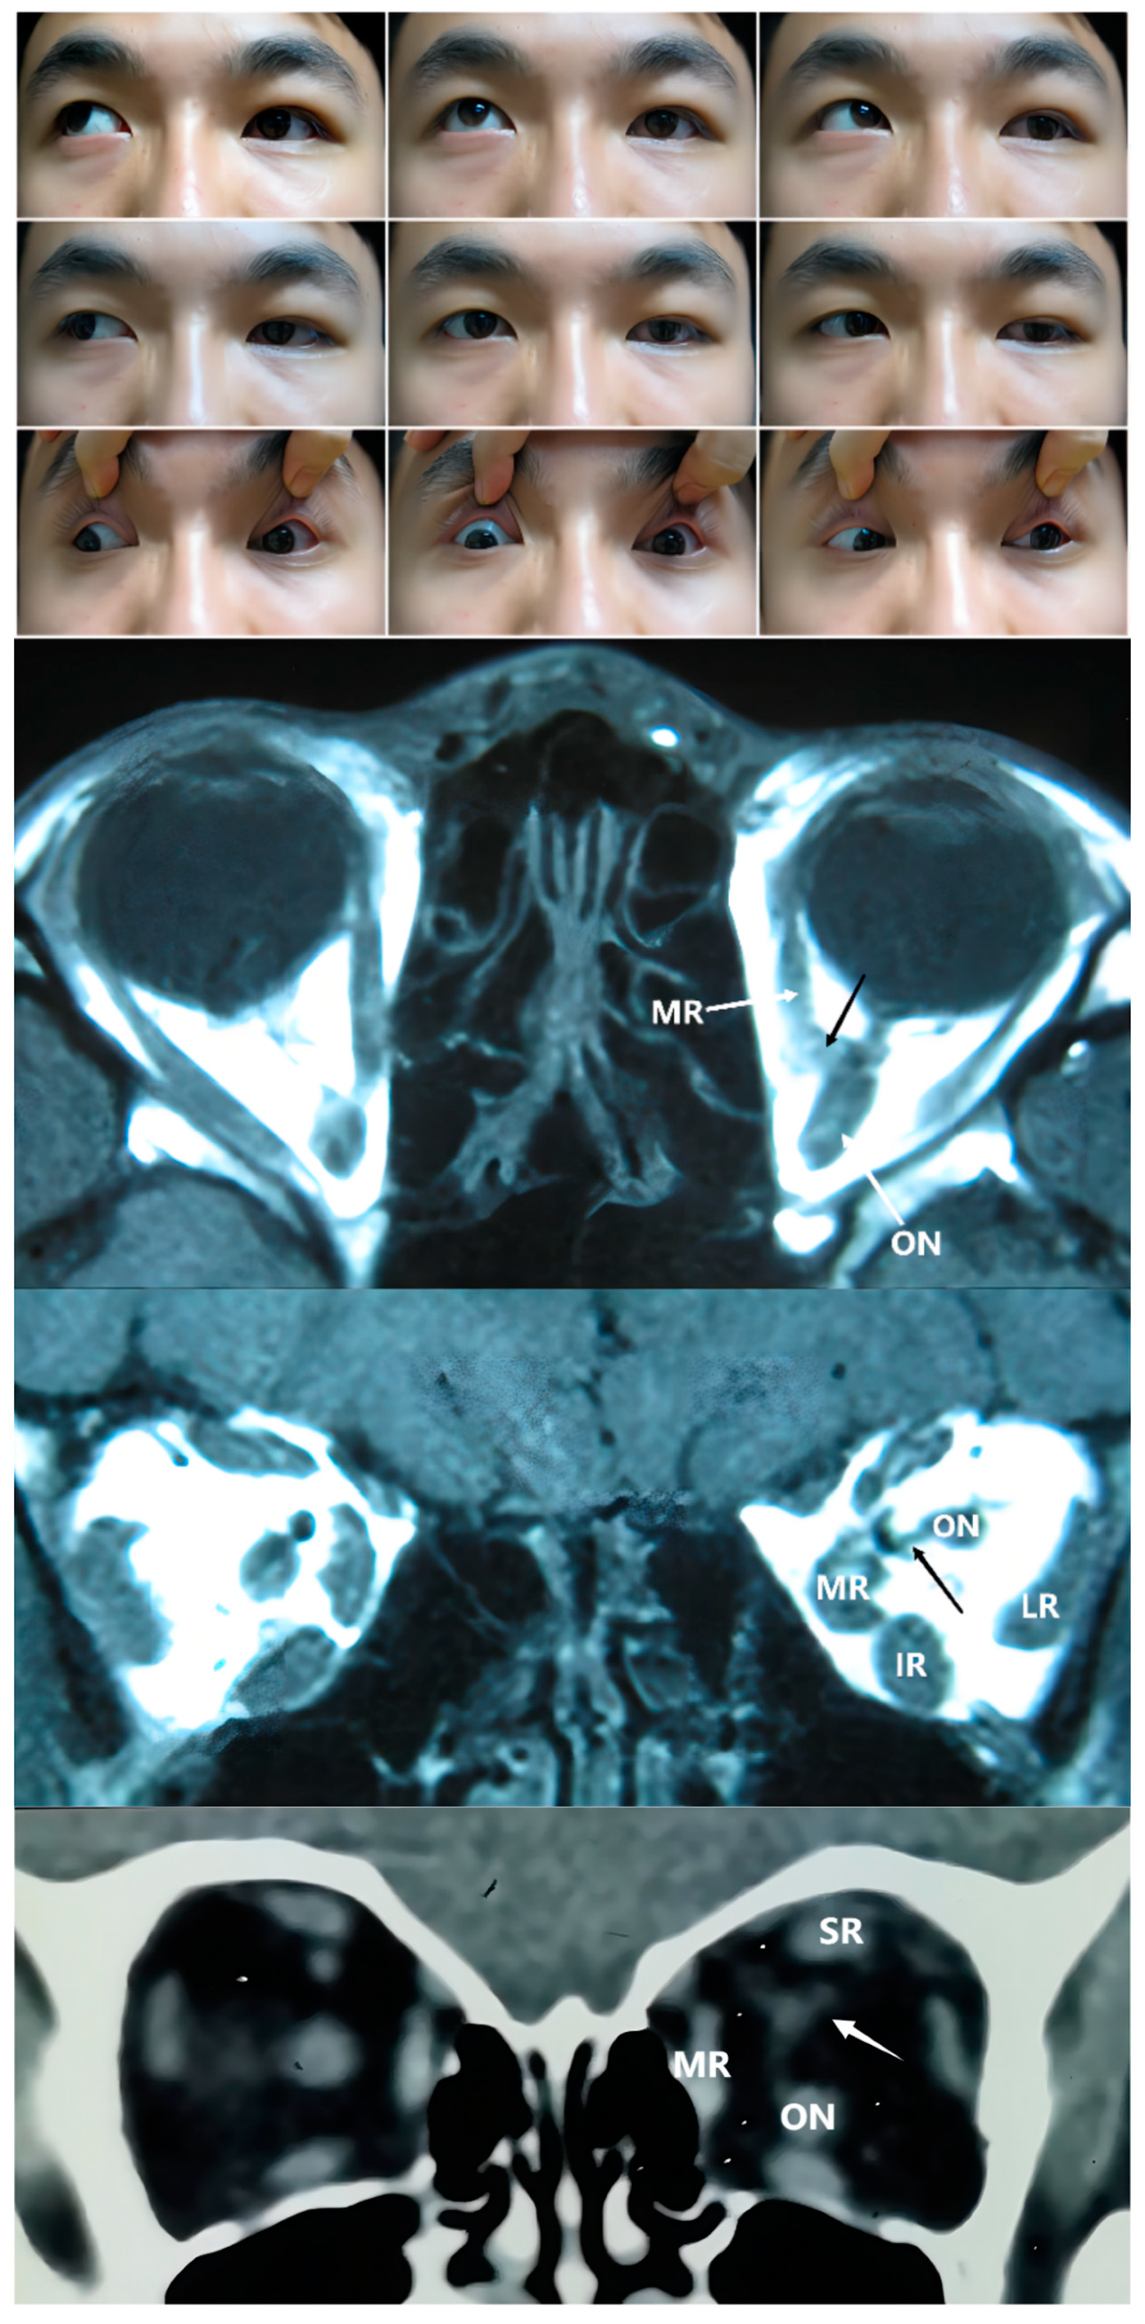

Figure 2. Upper Panel: Nine gaze photographs of Case 2 showing a 30 PD esotropia and -4 limitation in the abduction of the right eye. The right eye showed eyelid entropion, with palpebral aperture 2 mm larger than that of the left eye. Bottom Panel: T1 and T2 axial and a T2 coronal MRI of Case 2. Anomalies in EOM bands extended from the apex of orbit and connected with multiple recti. The right optic nerve was maldeveloped and its path was unclear.

The second type of SEOM we identified was that wherein the rectus split into multiple bands, which then connected to other ERMs. From axial imaging, we found an abnormal band originating from the Zinn ring, which sometimes accompanied recti or formed connections with other recti as they entered the orbit. In such cases, multiple abnormal connecting bands among recti, deformed recti, and unclear boundaries were observed in the coronal views. From a recent anatomic study, the Zinn ring was found to be composed of the IR, medial rectus (MR), and lateral rectus (LR), with the SR confirmed to have an independent origin. It seems that muscular or tendinous connections tend to form between the SR and other recti, such as in the type 2 cases in this study [20,21]. In a cadaveric study of a 68-year-old male conducted by Haladaj [16], the SEOM originated from the annulus of Zinn laterally to the ON, then separated into two heads, which inserted into the superior rectus (SR) and inferior rectus (IR). In Case 2, imaging revealed a supernumerary orbital muscular band from the apex of orbit to other recti muscles, including the SR, IR, LR, and MR (Figure 2). This 4-year-old girl showed moderate to severe limitations in ocular motility in all directions except adduction. In addition, all the accessory structures of the three patients classified as type 2 seemed to be closely related with the ON, and the BCVA in the involved eyes was very poor (4/20, counting fingers and hand movement, respectively).